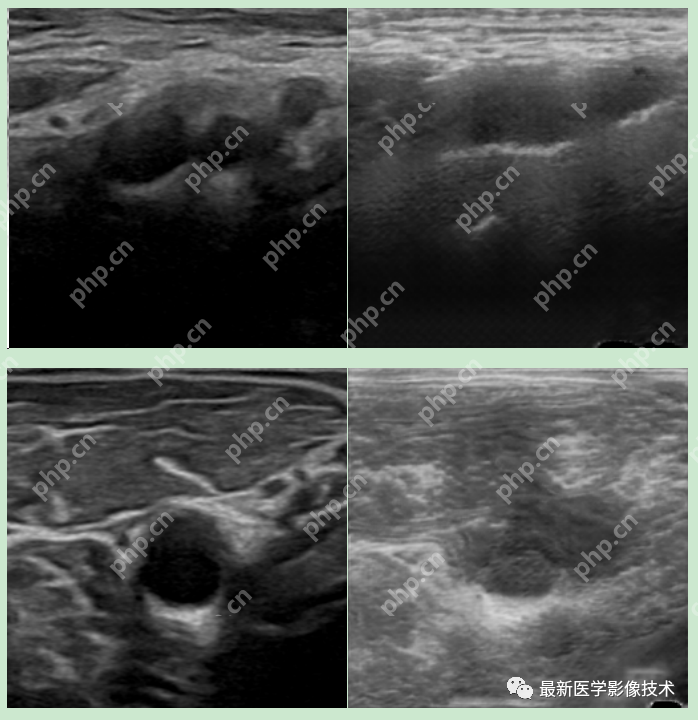

5、验证集部分生成结果

左图为低质量图像,中间为生成的高质量图像,右图为真实的高质量图像。